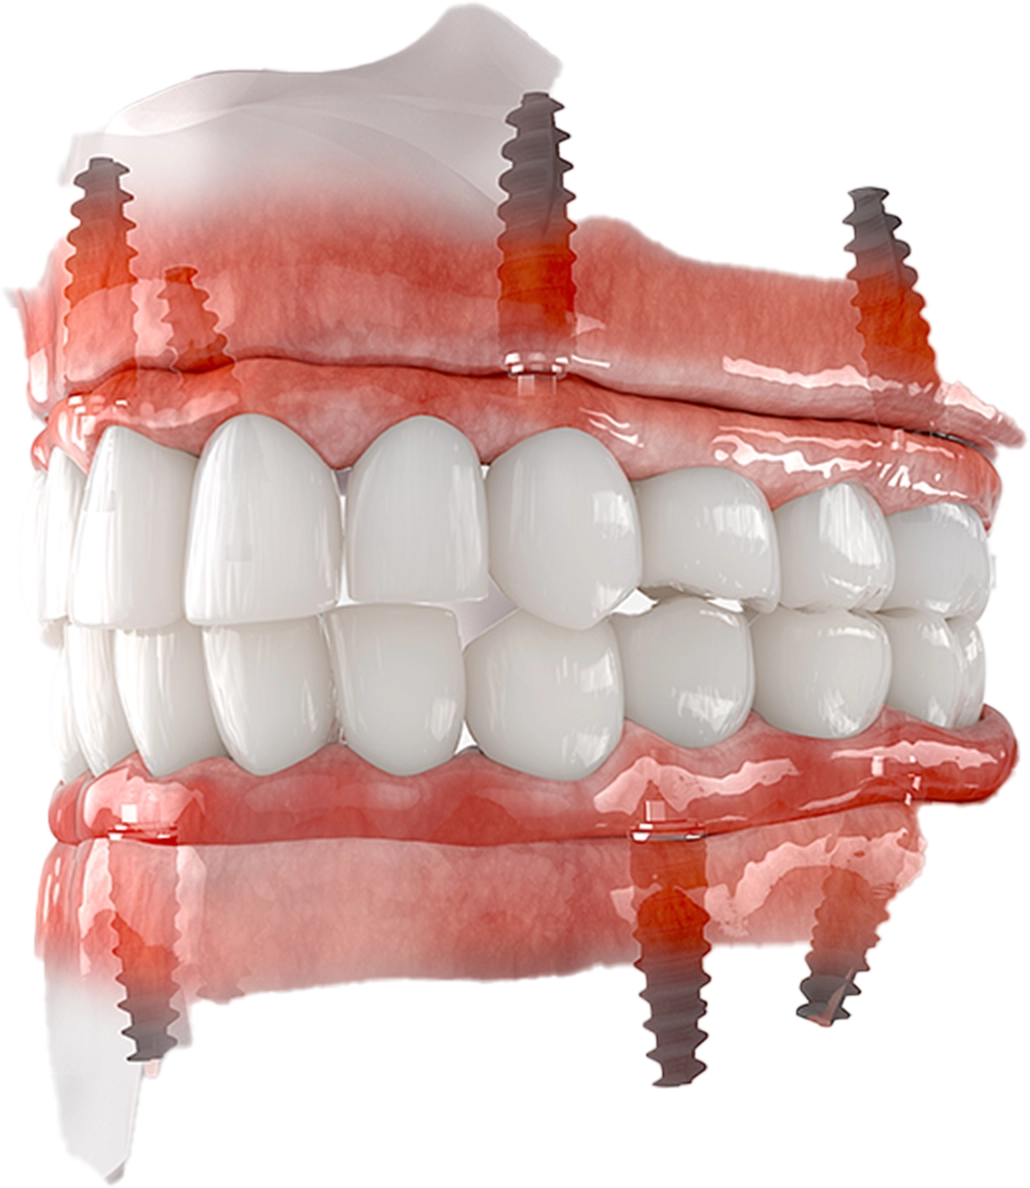

サージカルガイドとは?

インプラント埋入を精密

にする

マウスピース型ガイド

これまで、インプラント治療は技術の経験と勘によって位置や方向が決められて、フリーハンドで手術が行われていました。

より確実な埋入を行うために、考えられたのが、サージカルガイドを使用した治療です。

3次元のCTの上でインプラントを埋め込むためのシュミレーションを行なって、 定規のように、正確にインプラントが埋入できるマウスピース型のガイドを作成します。

これをサージカルガイドと呼びます。

サージカルガイドと専用のドリルを用いることで、インプラントを事前に撮影したCT画像で設定した理想的な位置に、正確にインプラントを埋めこむことが可能となります。